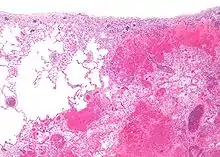

| Micrograph of a pulmonary infarct (right of image) beside relatively normal lung (left of image). H&E stain. | |

- Lung: Pulmonary infarction or lung infarction